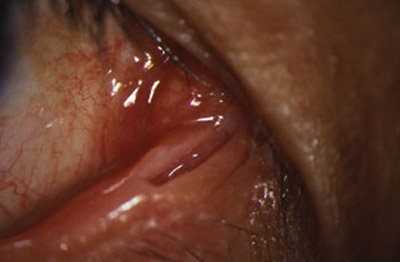

Hay casos en que por error, en véz de hacer la puntectomía vertical, se la realiza en forma horizontal , abriendo todo el canalículo de 5 a 8 mm. desde el punto lagrimal, lo cual causa una epífora permanente muy molesta.

Bajo microscopio (a 16 aumentos) y con anestésia local, Xilocaina al 2% con adrenalina, inyectada sub dérmica en el tercio interno del parpado inferior, canto medio, procedemos a evertir un poco el borde palpebral inferior con un aplicador de algodón, para exponer el area marsupializada del canalículo, dejando la luz mucosa ampliamente expuesta.

Con un trozo de cuchilla de afeitar, montada en un portacuchillas Barraquer, se practican dos incisiones horizontales, a lo largo de la porción marsupializada del canalículo, para independizar los planos anatómicos, separando así los bordes interno o muco-mucoso y externo o muco-cutaneo.